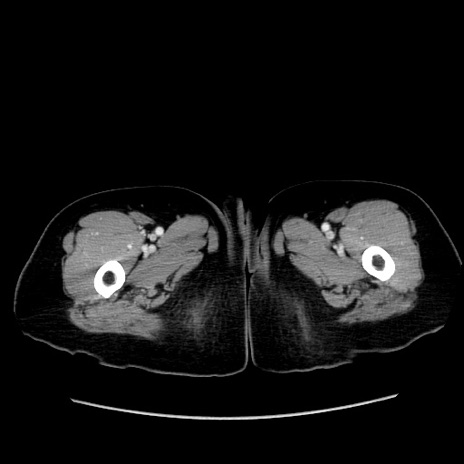

症例19(横断像)

【症例】80歳代女性

【主訴】下腹部痛

【現病歴】約8時間前より下腹部痛の出現あり、救急外来受診。

【既往歴】両側付属器切除

【身体所見】意識清明、下腹部正中に手術痕あり、その部位に一致して圧痛と反跳痛あり。腸蠕動音は亢進。

【データ】WBC 9300、CRP 0.15